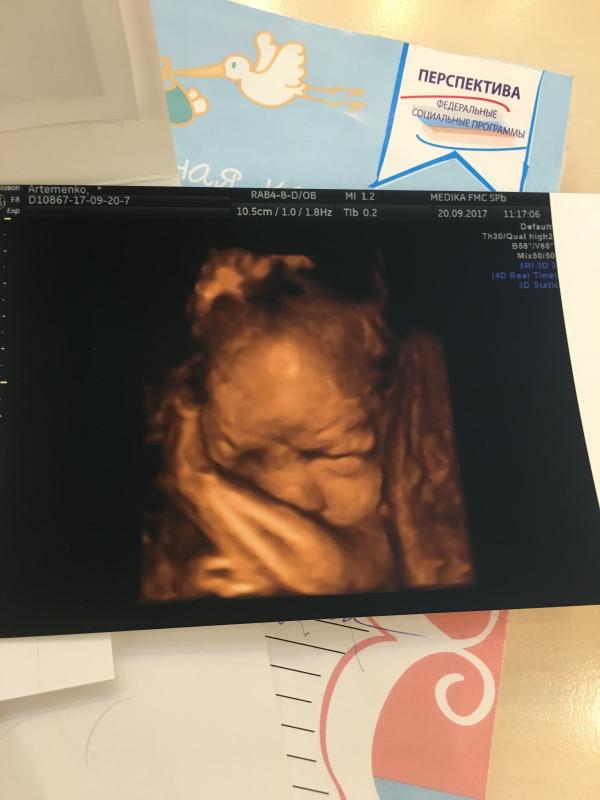

После сдачи пяти пробирок крови натощак, меня вдруг посетило озарение сходить на 3д УЗИ. Клиника была недалеко, нашлось свободное время как раз через час. Итоги- ГЭФ в сердечке н куда не делся, тазовое предлежание 😳 (ещё позавчера на осмотре лежала головой вниз), и на десерт старение плаценты 3ей степени 😳😳😳. Врач была немного грубовата в выражениях. Ляля как обычно прячется не просто закрывает ручками все что можно, но и уткнулась лицом мне в спину 🙈🙈🙈 успели сделать одну фотографию. Вот иду теперь по парку и думы думаю.